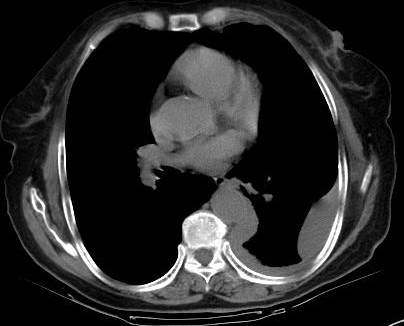

请上传纵隔窗。目前还是支技包裹性积液(明显梭形),即使是间皮瘤并积液也少梭形的。

从图片看,包裹性积液好象更合理,梭形,ct值3-5hu(在哪看到的?);胸膜间皮瘤如此规则,不多见。

左侧背部胸膜肥厚,伴包裹性积液,不考虑间皮瘤.

同意以上各位的高见,首先考虑包裹性积液,1.胸膜间皮瘤积液量一般较大,以游离性积液更为常见,2.可以看到增厚的胸膜结节